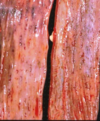

This is a picture of a rumen. What lesion is shown here?

Acute, multifocal to coalescing ulcerative ruminitis